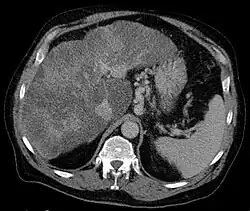

Gastric varices are dilated submucosal veins in the lining of the stomach, which can be a life-threatening cause of bleeding in the upper gastrointestinal tract. They are most commonly found in patients with portal hypertension, or elevated pressure in the portal vein system, which may be a complication of cirrhosis. Gastric varices may also be found in patients with thrombosis of the splenic vein, into which the short gastric veins that drain the fundus of the stomach flow. The latter may be a complication of acute pancreatitis, pancreatic cancer, or other abdominal tumours, as well as hepatitis C. Gastric varices and associated bleeding are a potential complication of schistosomiasis resulting from portal hypertension.